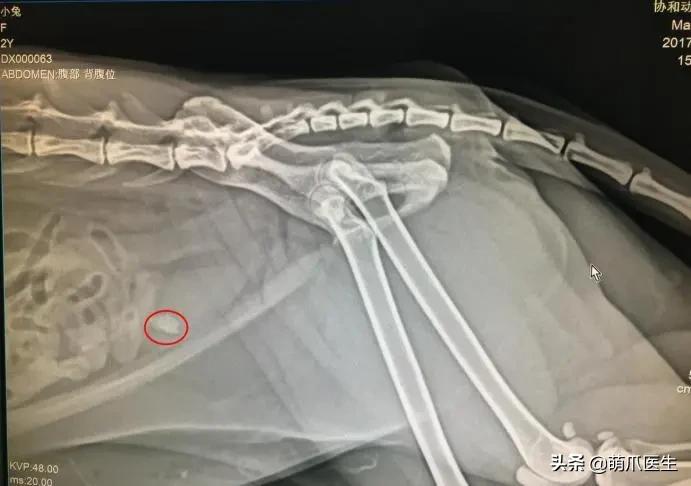

膀胱结石(X线片)